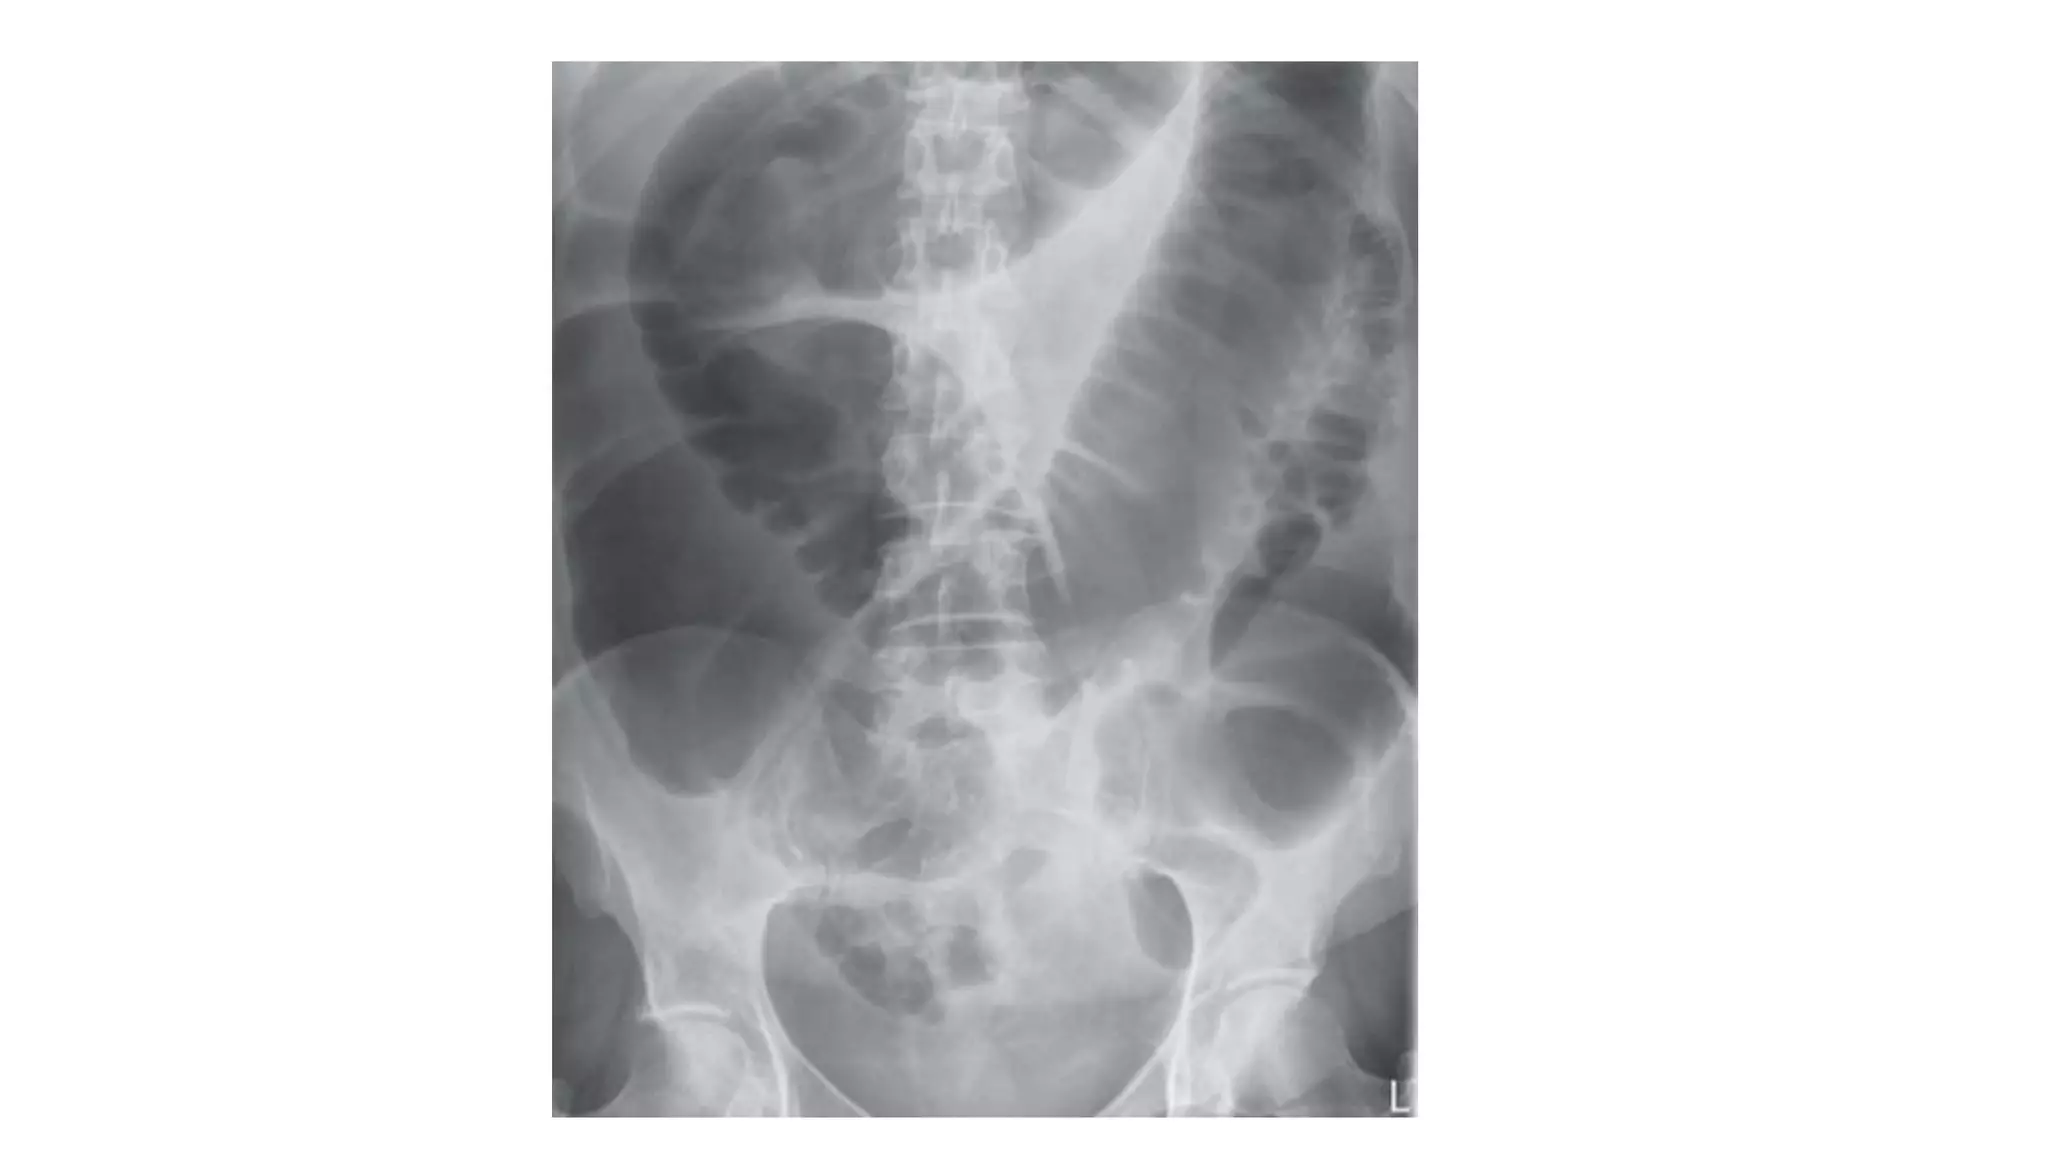

Radiological signs to look for:

• Dilation >3 cm: The small bowel is dilated if it measures over 3 cm in

diameter.

• Central location: The dilated loops are more likely to be centrally

located on the abdominal radiograph.

• Valvulae conniventes: These are the mucosal folds of the small

intestine. They are thin, closely spaced and classically seen as a

continuous thin line across the entire width of the bowel.

• Air fluid level in upright position

Who wants to be a hero ?

Pick up 3 findings

• #41 Note: The height of an adult vertebral body is approximately 4 cm. You can use this as a quick comparison to estimate the diameter of the bowel. Note: Large bowel tends to be peripherally located.

• #44 Note: The height of an adult vertebral body is approximately 4 cm. You can use this as a quick comparison to estimate the diameter of the bowel. Note: Large bowel tends to be peripherally located.